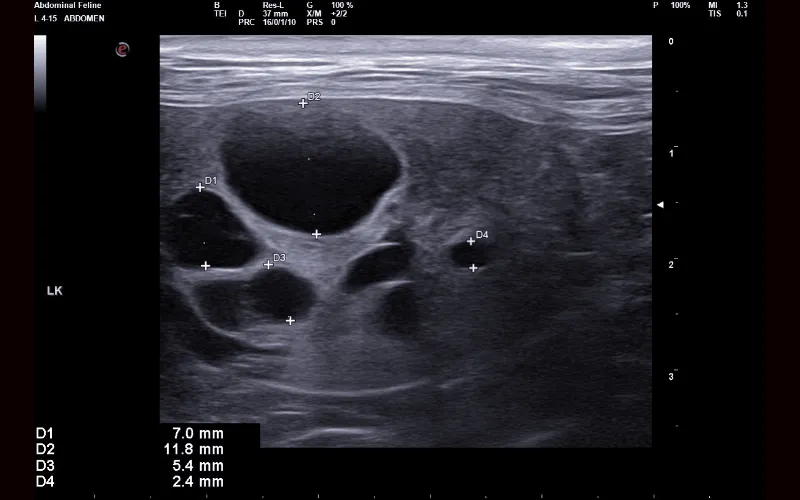

Different diseases and conditions create distinct patterns that become recognisable on ultrasound, even when physical examination or lab work has been inconclusive. Some findings are diagnostic in themselves, while others provide a strong indication of what is developing and the urgency with which it needs to be addressed.

Kidneys

Ultrasound allows us to examine internal organs without surgery. It helps identify changes in tissue structure and assess how organs interact with each other.

Ultrasound can evaluate abdominal organs, soft tissues and other internal structures. This imaging technique helps us look for abnormalities that may affect a cat’s health.

Ultrasound findings can clarify whether disease is localised or affecting multiple organs. This information helps us determine the most appropriate next steps for diagnosis or treatment.